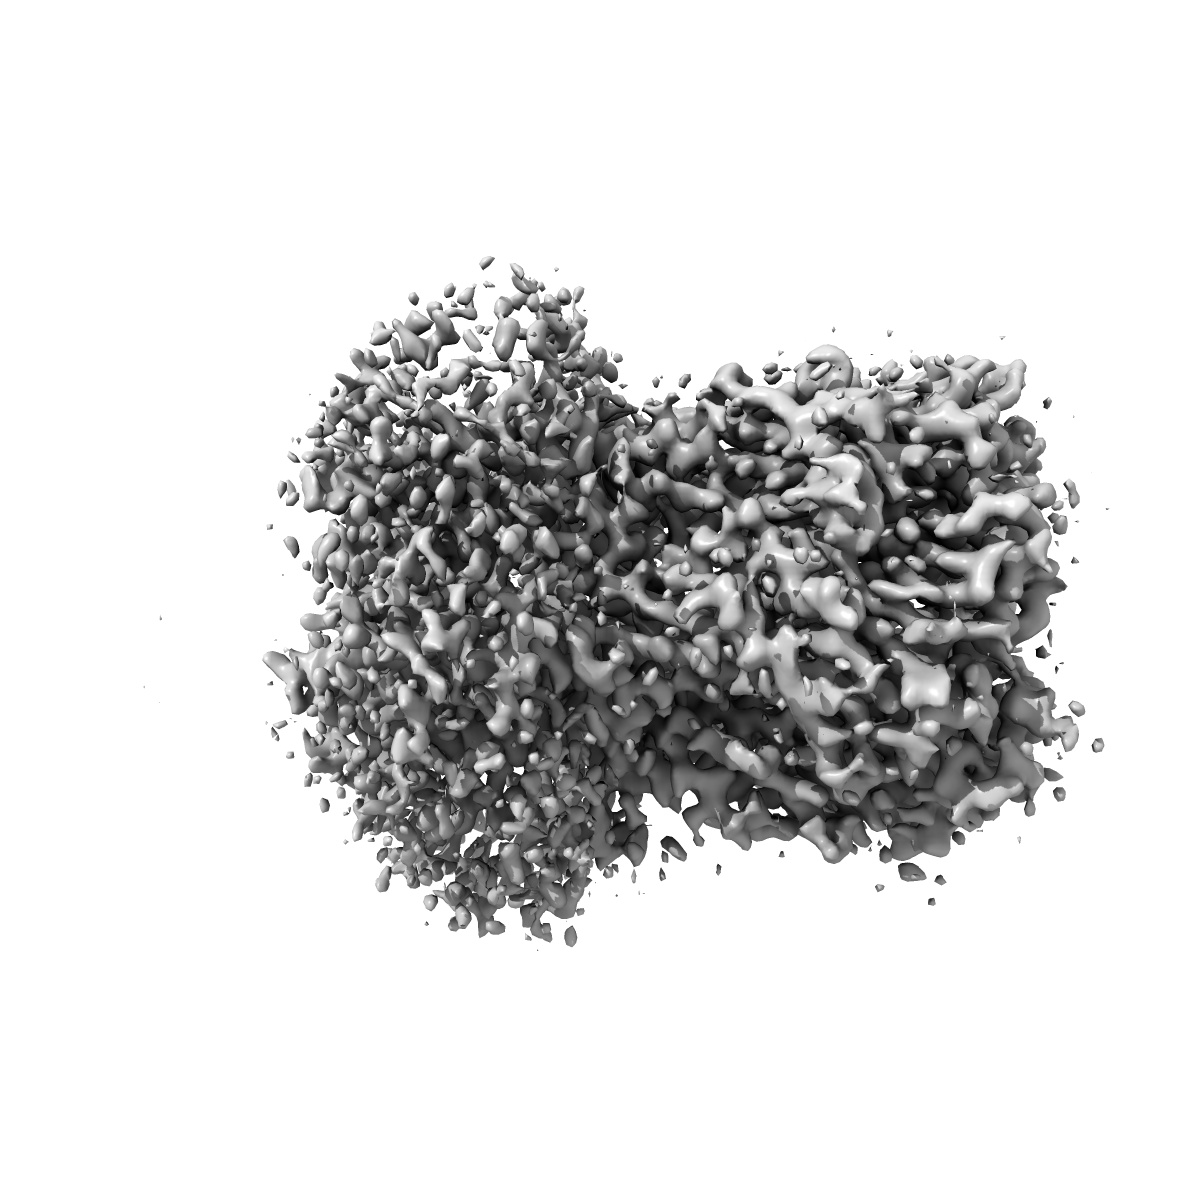

Cyro-EM structure of human Glycine Receptor alpha2-beta heteromer, glycine bound, (semi)open state

Sample: Glycine receptor alpha2-beta heteromer, glycine bound, open state

Characterization of the subunit composition and structure of adult human glycine receptors

Yu H, Bai X-C, Wang W

(2021) Neuron , 109 , 2707 - 2716